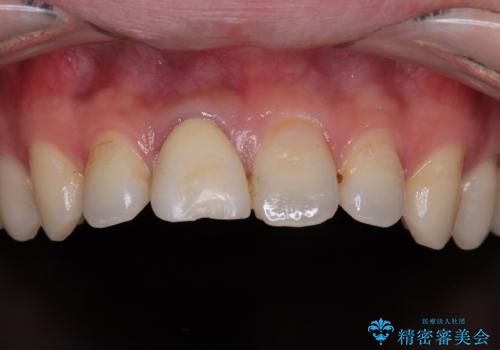

- 数年前に前歯のセラミック治療を行い、そのやり替えを希望して来院された患者様です。

先端が欠けてしまっていて、色も少し不自然な印象があります。

空隙がある歯並び改善のため、矯正治療も提案しましたが希望せれず、隣の歯も一緒に被せものにして、

大きさをそろえることも希望されなかったため、一本だけやり替えていくととしました。